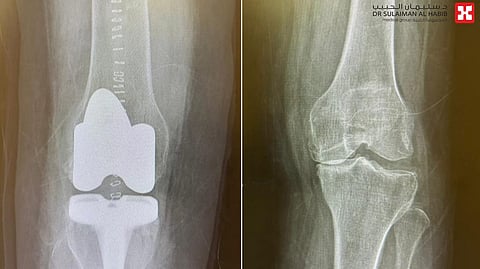

وأضاف أن الفريق الطبي اطلع على ملفها الطبي، وأخضعها لعدة فحوصات دقيقة، شملت التصوير بالأشعة السينية الرقمية Digital X-rays والتحاليل المخبرية، وقد أوضحت النتائج وجود ميلان في الساقين وخشونة شديدة من الدرجة الرابعة في مفصلي الركبة.

وأوضح د. البراك أنه تم وضع خطة علاجية متكاملة، في الجزء الأول منها وتم استبدال مفصل الركبة اليسرى، ومن ثم في الجزء الثاني من الخطة تم استبدال مفصل الركبة اليمنى، واستغرقت العمليتان "120" دقيقة وتكللتا، ولله الحمد بالنجاح دون أية مضاعفات، حيث نقلت المراجعة مباشرة إلى جناح التنويم، واستطاعت المشي بعد العملية بساعات بمساعدة العلاج الطبيعي، وقد تلقت الرعاية الطبية الفائقة طوال أيام تنويمها، قبل أن تخرج إلى منزلها وهي بصحة جيدة، وعادت للمراجعة الطبية بالعيادة بعد عدة أسابيع وهي تمشي دون مساعدة، كما أنها تخلصت من كافة الأعراض التي عانت منها سابقاً.